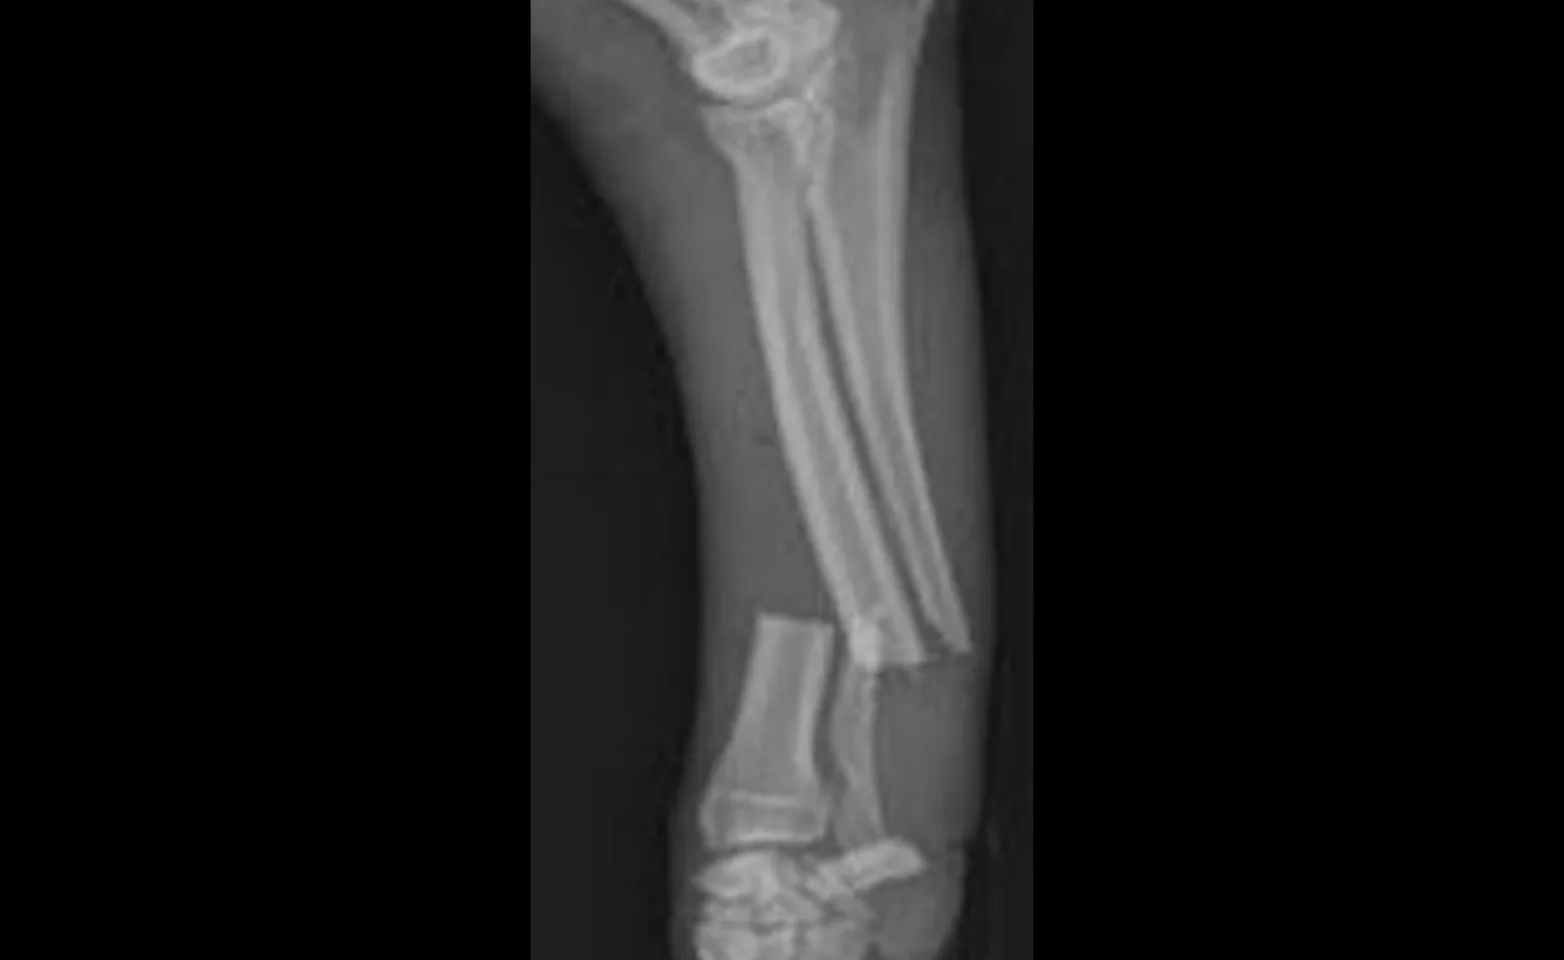

The distal radius and ulna of toy breed dogs has been shown to have a higher than normal incidence of abnormal healing of the bone following fracture repair.

Placement of a cast or splint alone or combined with an IM pin does not provide for rotational stability and has a high incidence of brous nonunion formation. Ideally, the fracture segments should be anatomically reduced and stabilized with a plate and screws.